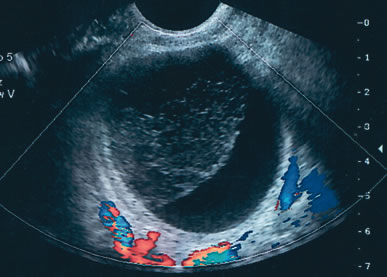

Fig. 2. A biloculated 6-cm mass in a premenopausal woman. The upper cyst, which is filled with low-level echogenicity, is typical of the pattern seen in endometriotic cysts. After 8 weeks of expectant management, the lower cyst resolved. At surgery, the residual cyst was identified as an endometrioma.